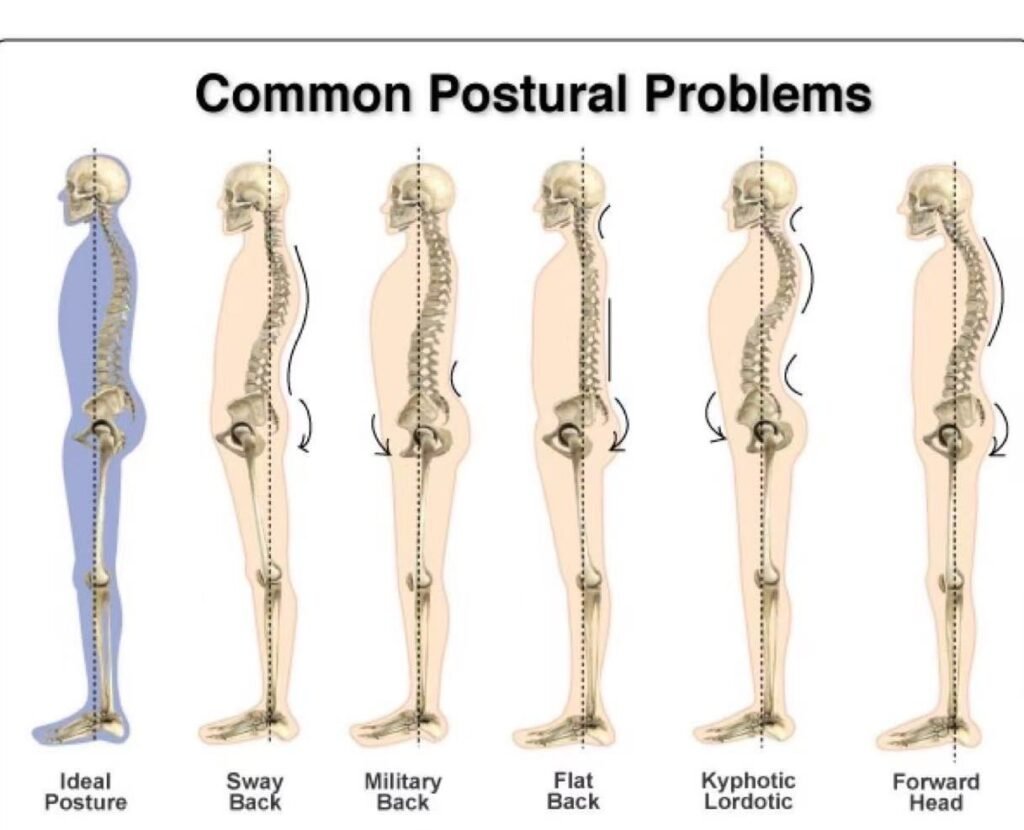

Here, we see the before and after images of a typical treatment. At first glance, it may appear that the patient’s kyphosis has been corrected—but what’s actually happened is that the thoracic curve has been flattened, resulting in a condition known as flat back syndrome.

This isn’t true correction—it’s simply trading one pathological posture for another.

In fact, the kyphosis hasn’t been corrected at all. If you removed the compensatory flat back, the kyphotic curvature would reappear. So now, instead of addressing a single issue, the patient is left with two structural problems layered on top of each other.

If symptomatic changes occur after kyphosis is displaced from its original structural layer into a newly formed flat back pattern, the critical factor becomes the individual’s proximity to their biomechanical threshold. This threshold represents the point at which the body’s compensatory mechanisms can no longer counteract the altered internal pressure dynamics. Once surpassed, external manipulations not only lose effectiveness but may accelerate structural degeneration. At this stage, only a true corrective intervention—one that restores internal balance and pressure distribution—can address the deeper compensatory dysfunctions induced by such shifts.

True correction must be both safe and accurate—not just symptom-driven or visually appealing. Otherwise, you risk replacing one dysfunction with another, and possibly creating an even bigger problem in the future.

—not as popular, but equally problematic. Instead of causing the spine to collapse into flexion, this method forces the body to collapse into extension as a form of compensation.

These techniques typically involve a rapid, forceful thrust directed at the upper thoracics or the lumbar spine. or the person is lifted into extension and then some degree of pressure is applied onto the spine to get a crack noise as the spinal facets jam together into this forced extension and external spinal pressure—This external pressure applied over a fulcrum using leverage. This type of spinal manipulation traps the vertebrae between a collapsing structure beneath the practitioner’s hand and adjacent vertebrae being shoved into extension. It’s the same type of stress people experience when doing deep backbends or rolling their spine over a foam roller. The result? A swayback posture, where the spine gets jammed between two opposing forces: the collapse beneath, and the hyperextension above.

The critical flaw in this technique is the misguided belief that collapsing someone forward into flexion is bad, but collapsing the spine backward into extension is somehow acceptable—even beneficial. But that’s simply not true. What’s really happening is a forced spinal reversal, one that drives the body into pathological extension.

It may look like a postural improvement on the surface, but it’s an illusion. This type of forced reversal doesn’t correct the underlying issue—it just shifts the problem to another part of the spine. Over time, the body pays the price.

The takeaway from these two structural manipulation techniques is clear: when we attempt to shift the body’s structure using external force, we’re left with only two possible outcomes—and both are pathologically flawed.

In one direction, the force collapses the spine forward, resulting in a flattened, rigid “flat back” posture. In the other, it drives the spine into exaggerated extension, creating spinal reversals and swayback patterns.

No matter the intention, external force leads to structural distortions in either direction—forcing the body into unnatural postures rather than restoring true alignment. These aren’t corrections; they’re compensations. And over time, they can cause more harm than help.